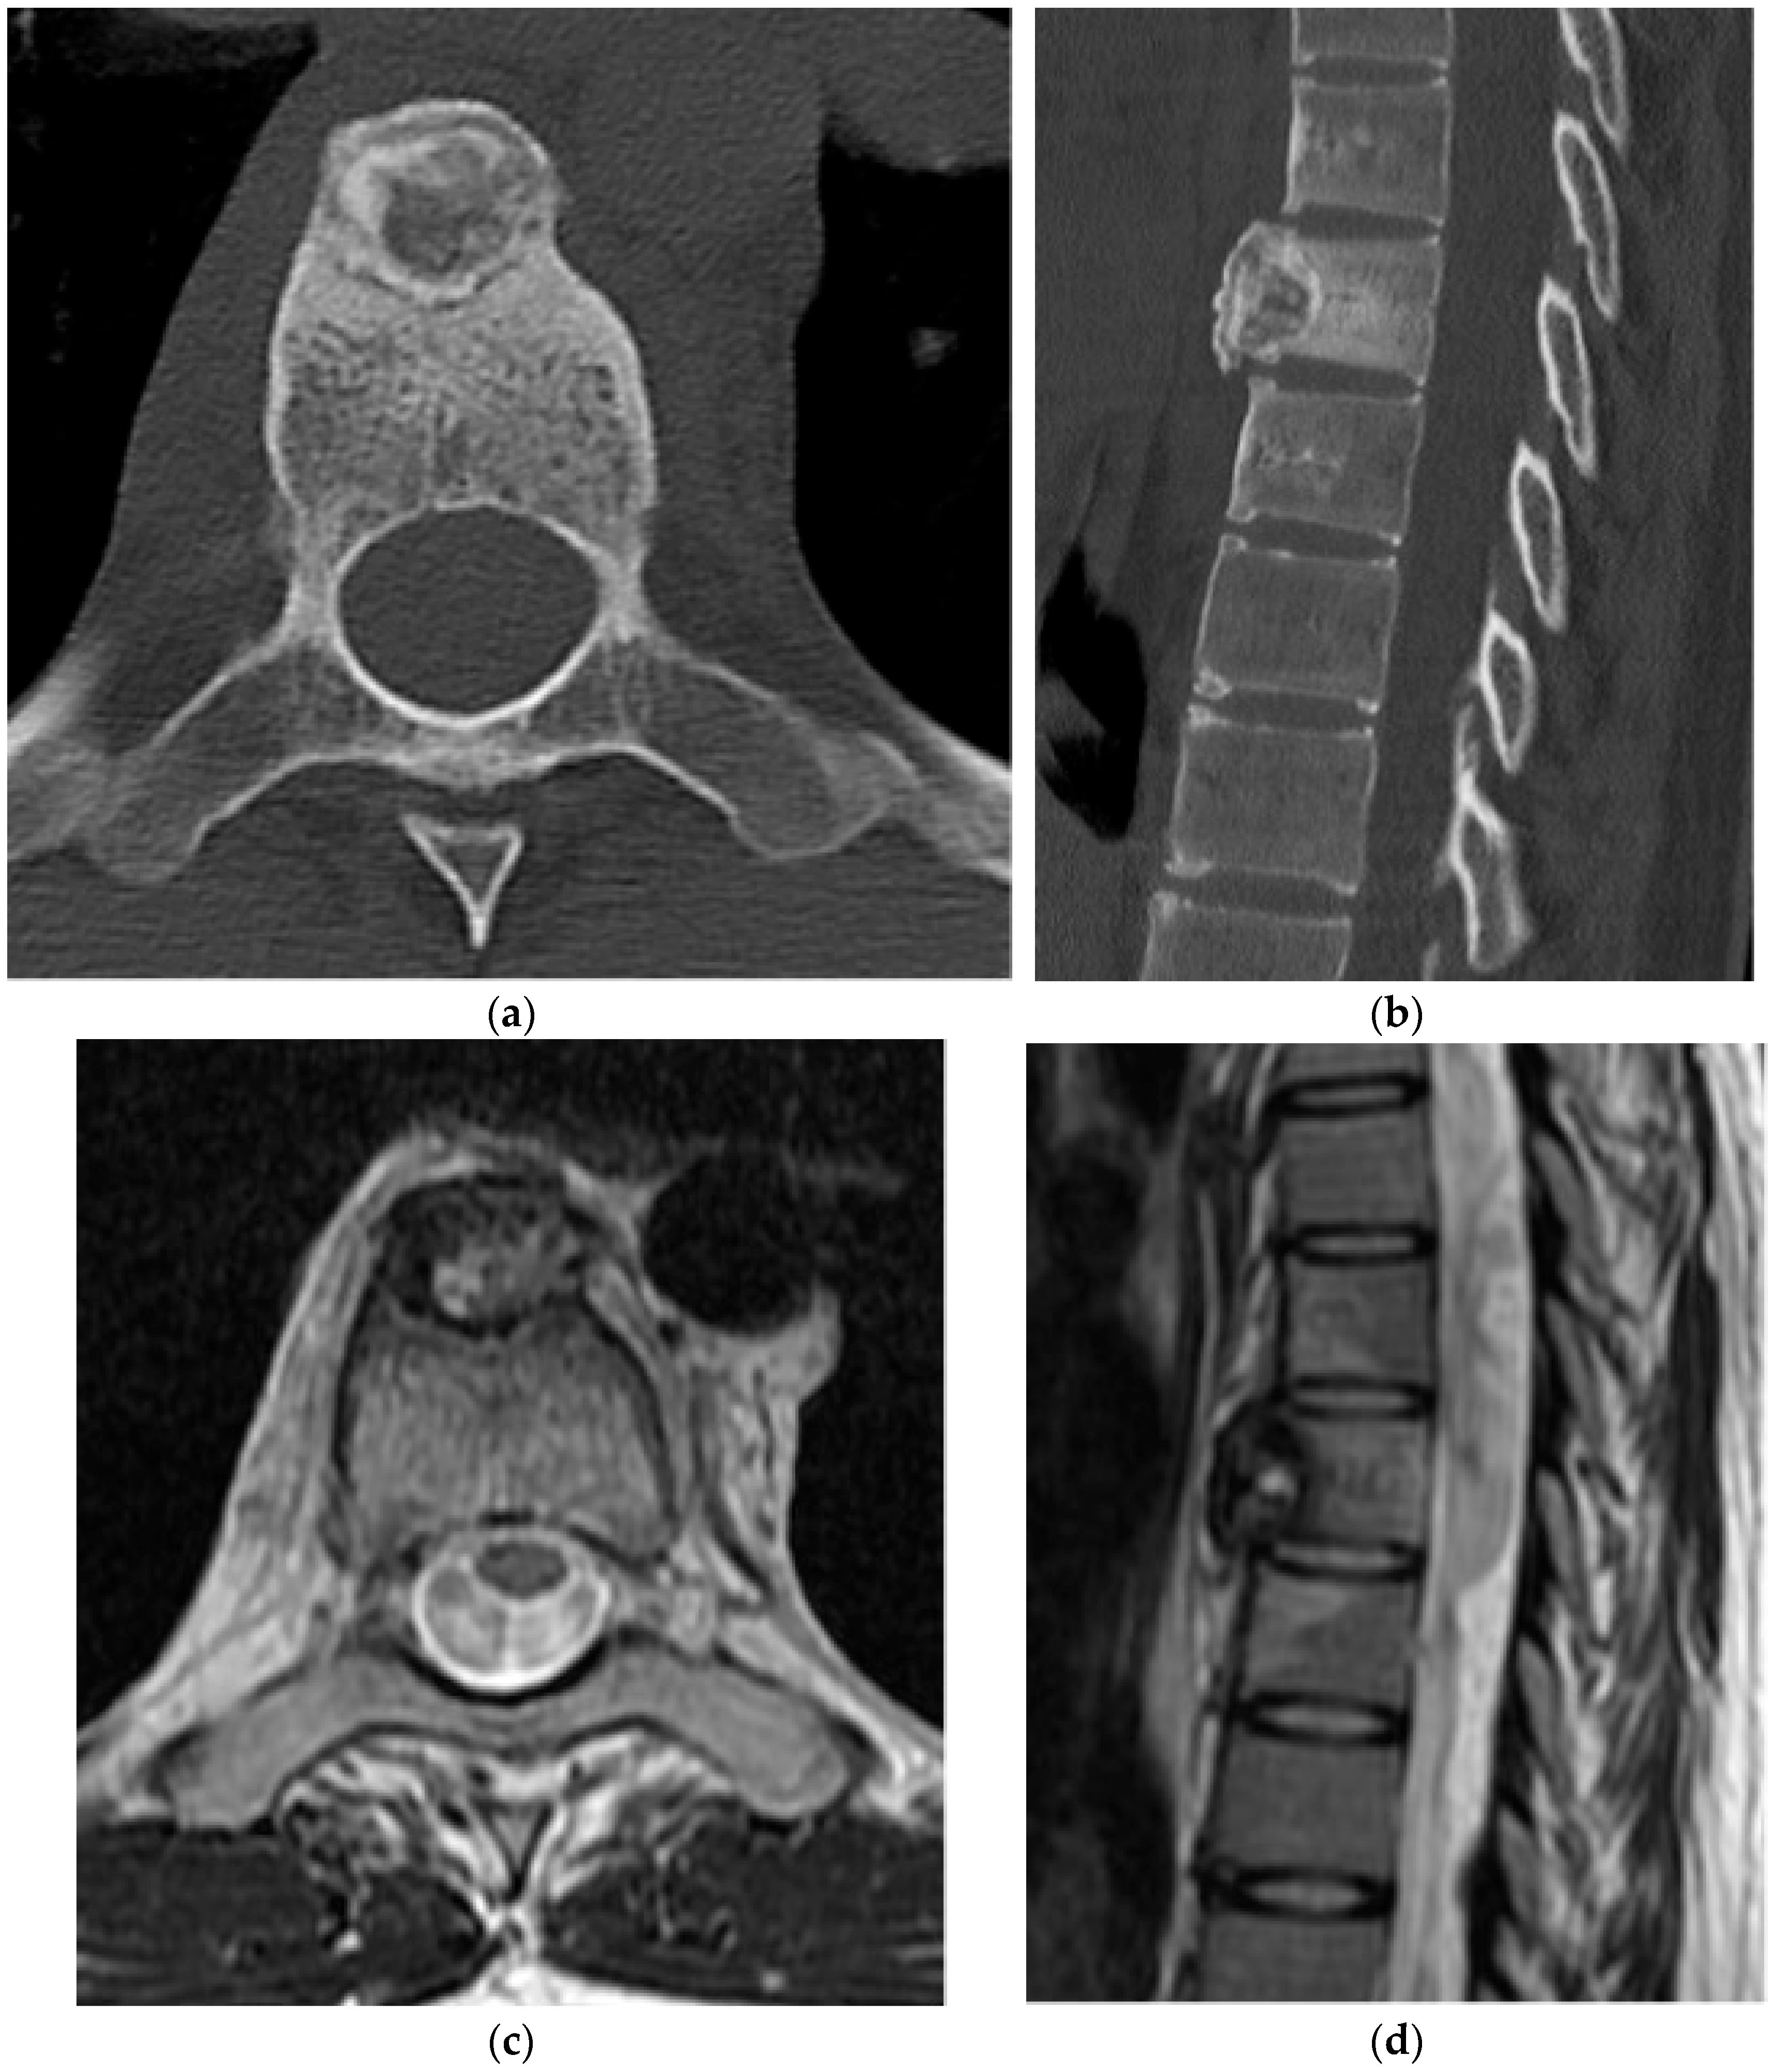

2.2.1. Osteochondroma

2.2.2. Chondroblastoma